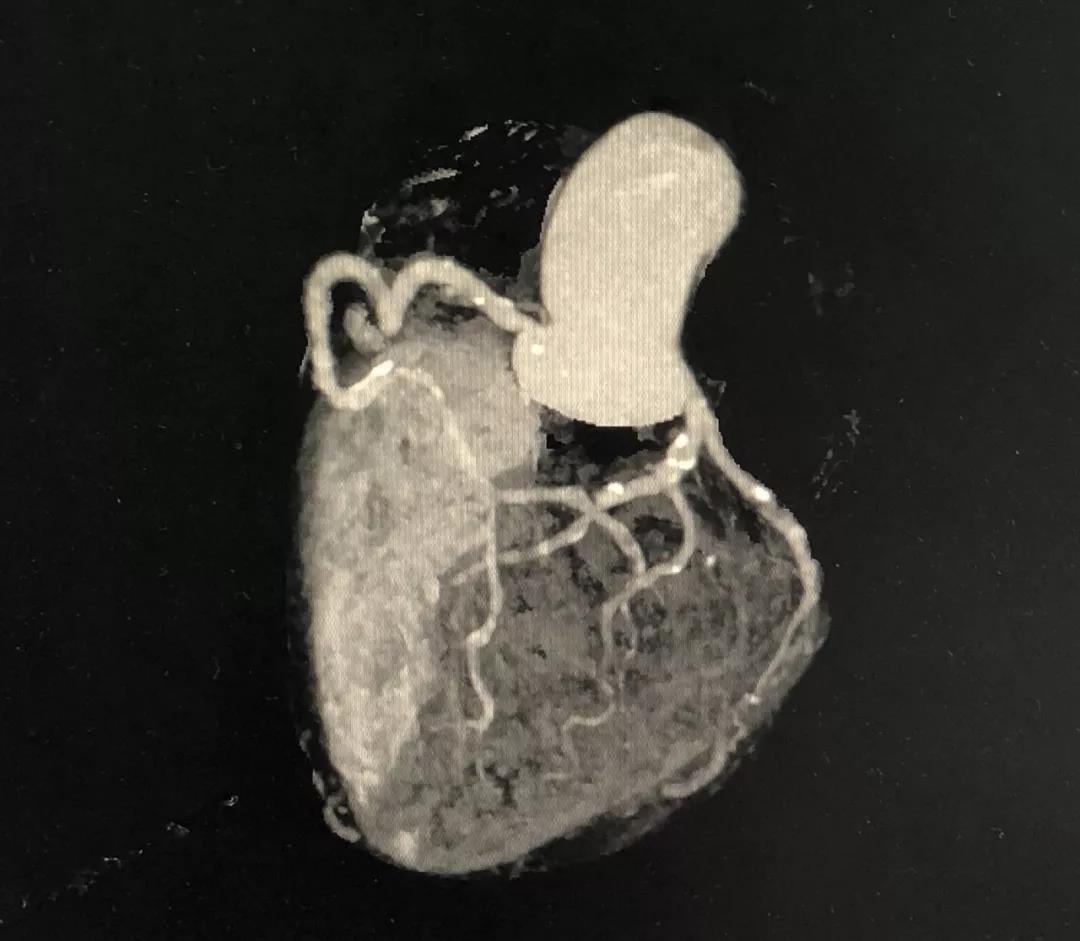

冠状动脉CTA

CCTA LAD病变特点:

近段血管较直

中远段血管偏细

中远段血管病变弥漫

病变段扭曲不很明显

病变段无重要分支发出

病变血管段有局灶点状钙化

CCTA的指导价值

药物洗脱球囊最核心的操作要领:一是充分的斑块预处理,二是药物球囊迅速到达目标病变位置,从而实现最有效的药物定点释放。其中,CCTA的评估功能不容小觑。结合上面的病例,术前CCTA检查的必要性如下:

1、明确了LAD病变位于血管的中远段,比较弥漫,病变段血管整体偏细,是应用药物球囊的适应症;

2、根据CCTA检查的结果,知晓病变的情况,预先准备好相应型号的药物洗脱球囊;

3、病变段血管为局灶性钙化,提示病变的预处理应该会很顺利;

4、病变近段的血管较直,相对健康,药物球囊入路通畅;

5、左主干无钙化,前分叉正常,为选用7F指引导管和/或使用延长导管提供了机会。

一句话,CCTA提示LAD中远段的小血管病变,可以使用药物洗脱球囊处理(给术者吃了颗定心丸)。